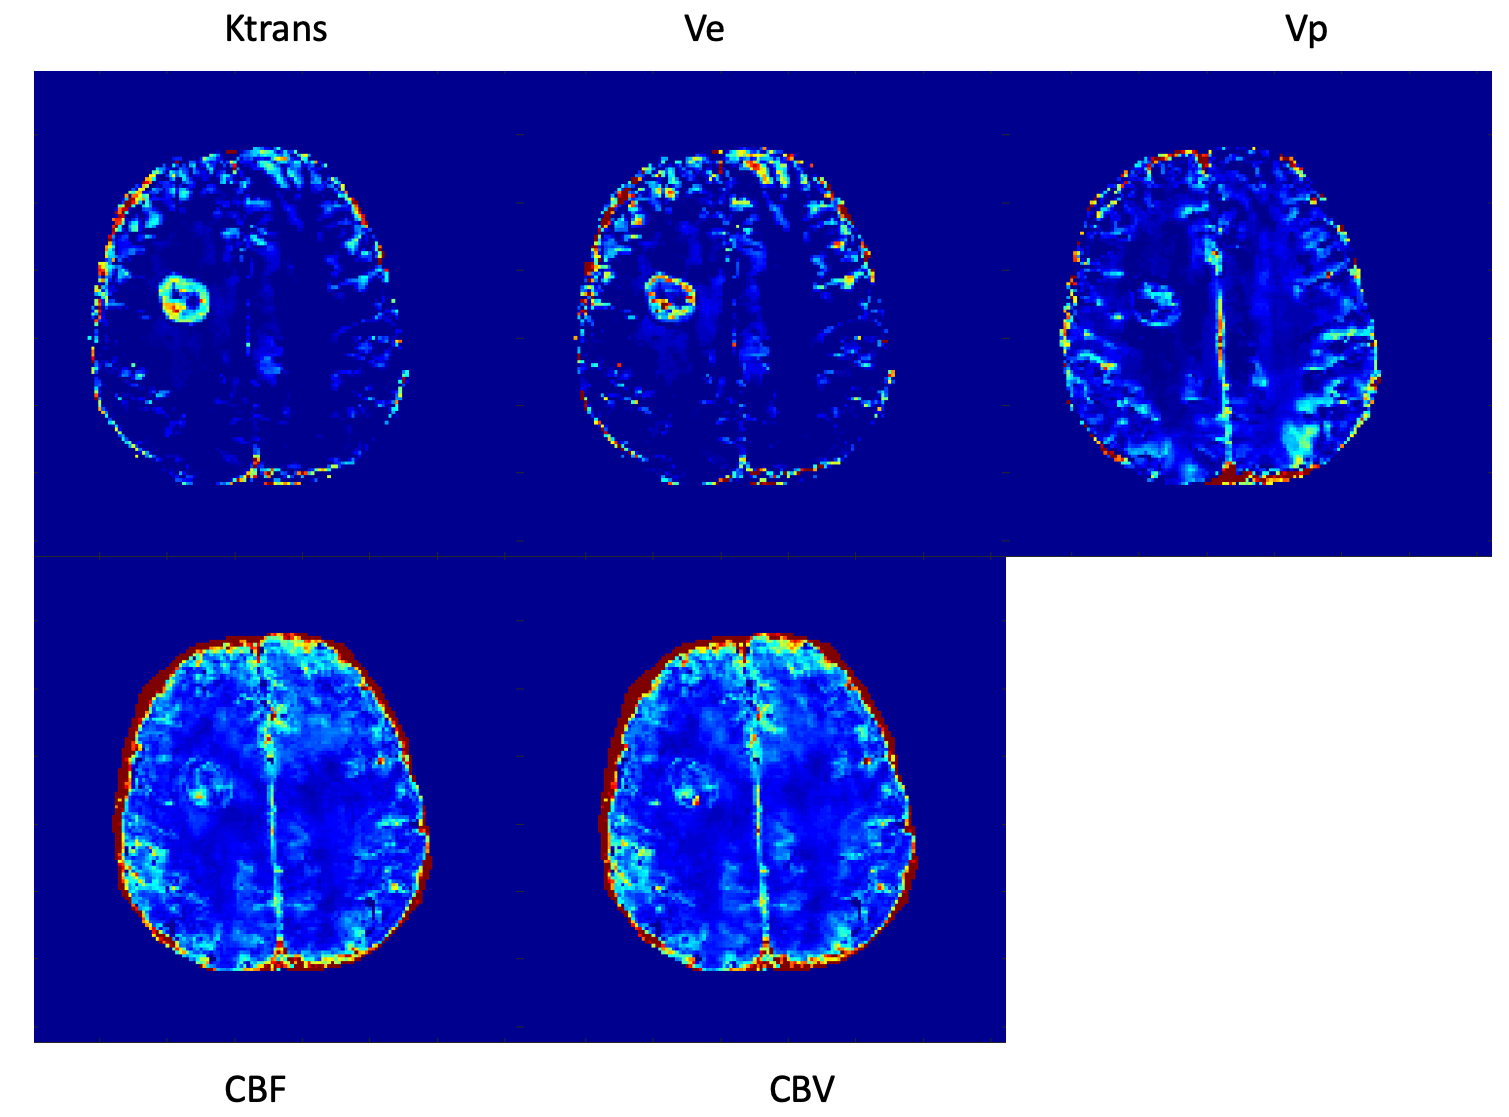

Figures 3 and 4 show examples of multiparametric MR images of a patient with brain metastases (lung cancer) and a patient with brain metastases (pulmonary sarcomatoid), respectively.

Figure 3. MT-DICE images of a patient with brain metastases due to lung cancer. Heterogeneously increased Ktrans, Vp, Ve, CBV, and CBF are shown.